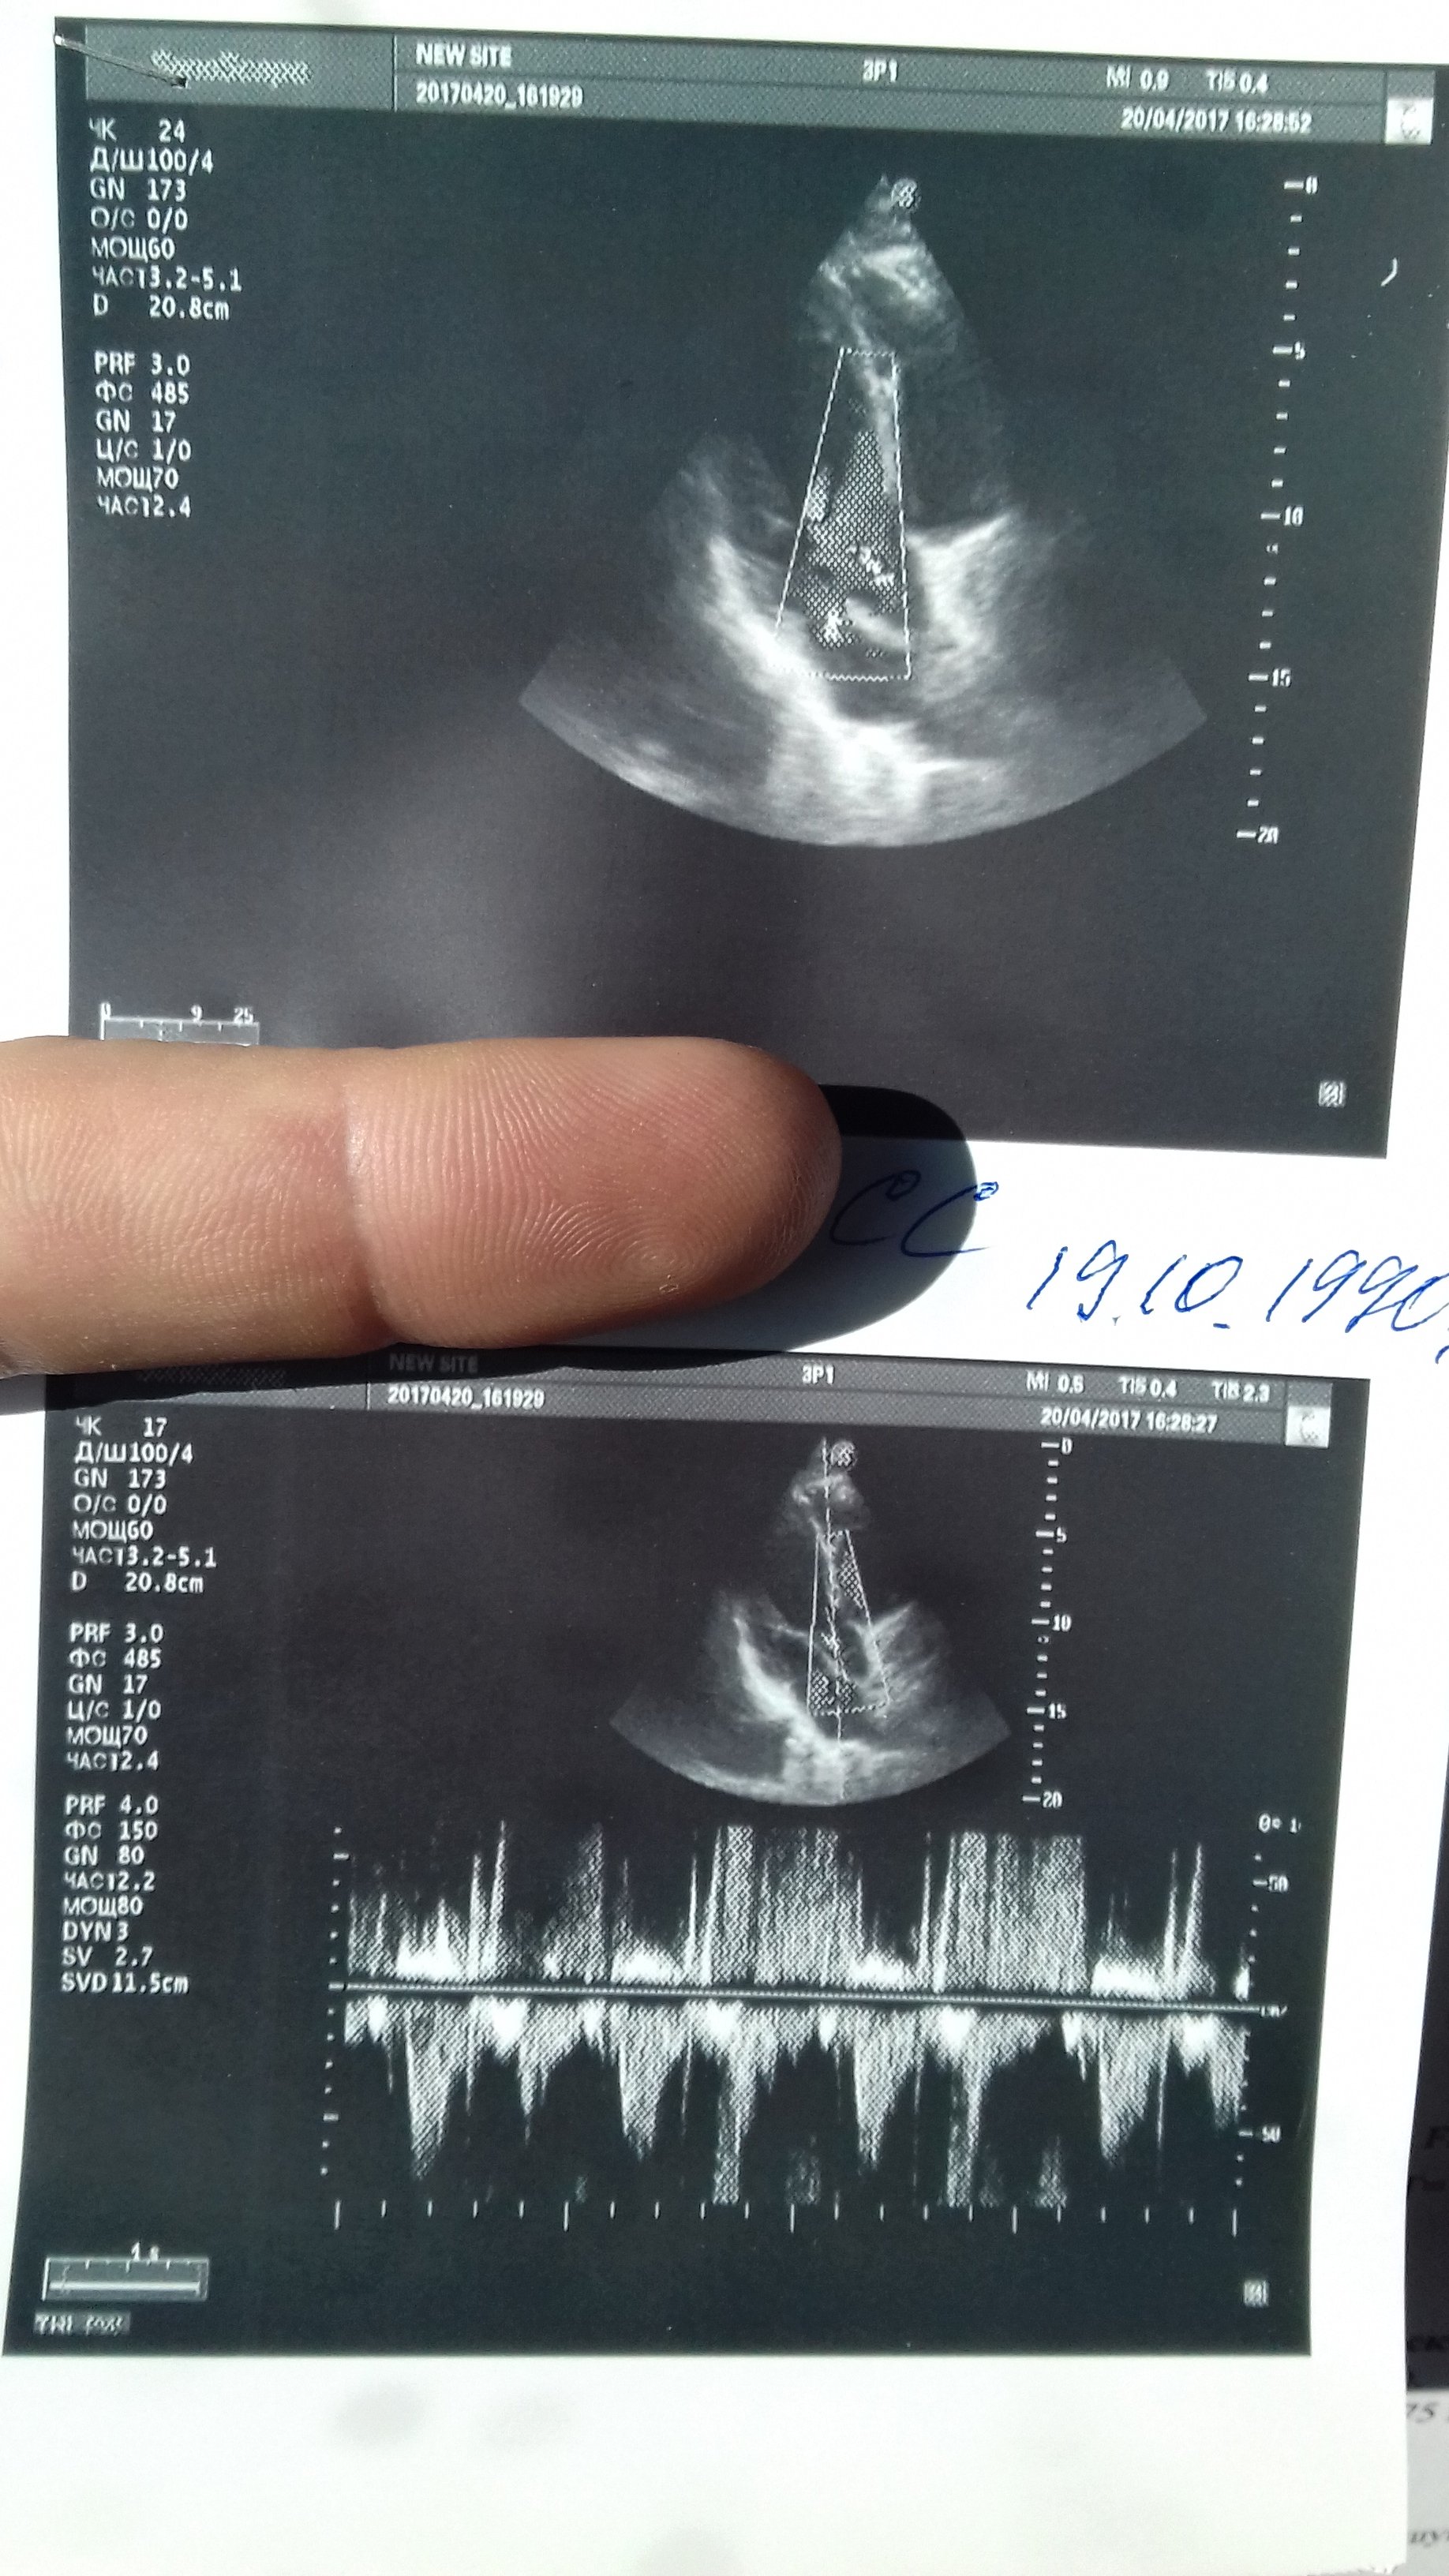

Ветка спортивного кардиолога

Тема в разделе "Медицинские консультации", создана пользователем ВЕЖЛИВЫЙ, 19 ноя 2016.